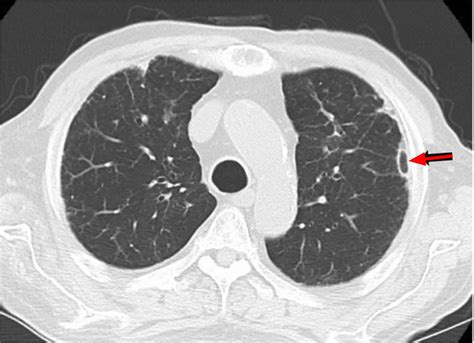

A lung nodule is defined as a growth measuring less than 3 centimeters in diameter. If the growth is larger than 3 centimeters, it is typically classified as a lung mass, which requires a more urgent diagnostic approach. These nodules can be caused by various factors, including old infections, inflammation, or scar tissue. While the term "lung nodule" might sound alarming, it is important to remember that they are often incidental findings discovered during scans performed for completely unrelated reasons, such as a routine physical or after a minor injury.

Determining whether a nodule requires treatment depends on its appearance, size, and your personal medical history. Physicians use several criteria to assess the risk of malignancy. For example, solid nodules with smooth borders are generally less concerning than those with irregular or "spiculated" edges. The following table summarizes how medical professionals categorize risk factors associated with these findings.

| Size | Less than 8mm | Greater than 8mm |

| Appearance | Smooth, well-defined | Irregular, spiculated |

| Growth Rate | Stable over 2 years | Rapid doubling time |

If your doctor discovers a nodule, they will likely start with a "watch and wait" approach. This involves periodic surveillance using low-dose CT scans to monitor the nodule for changes in size or density. If the nodule remains stable over two years, it is typically deemed benign and no further action is required.